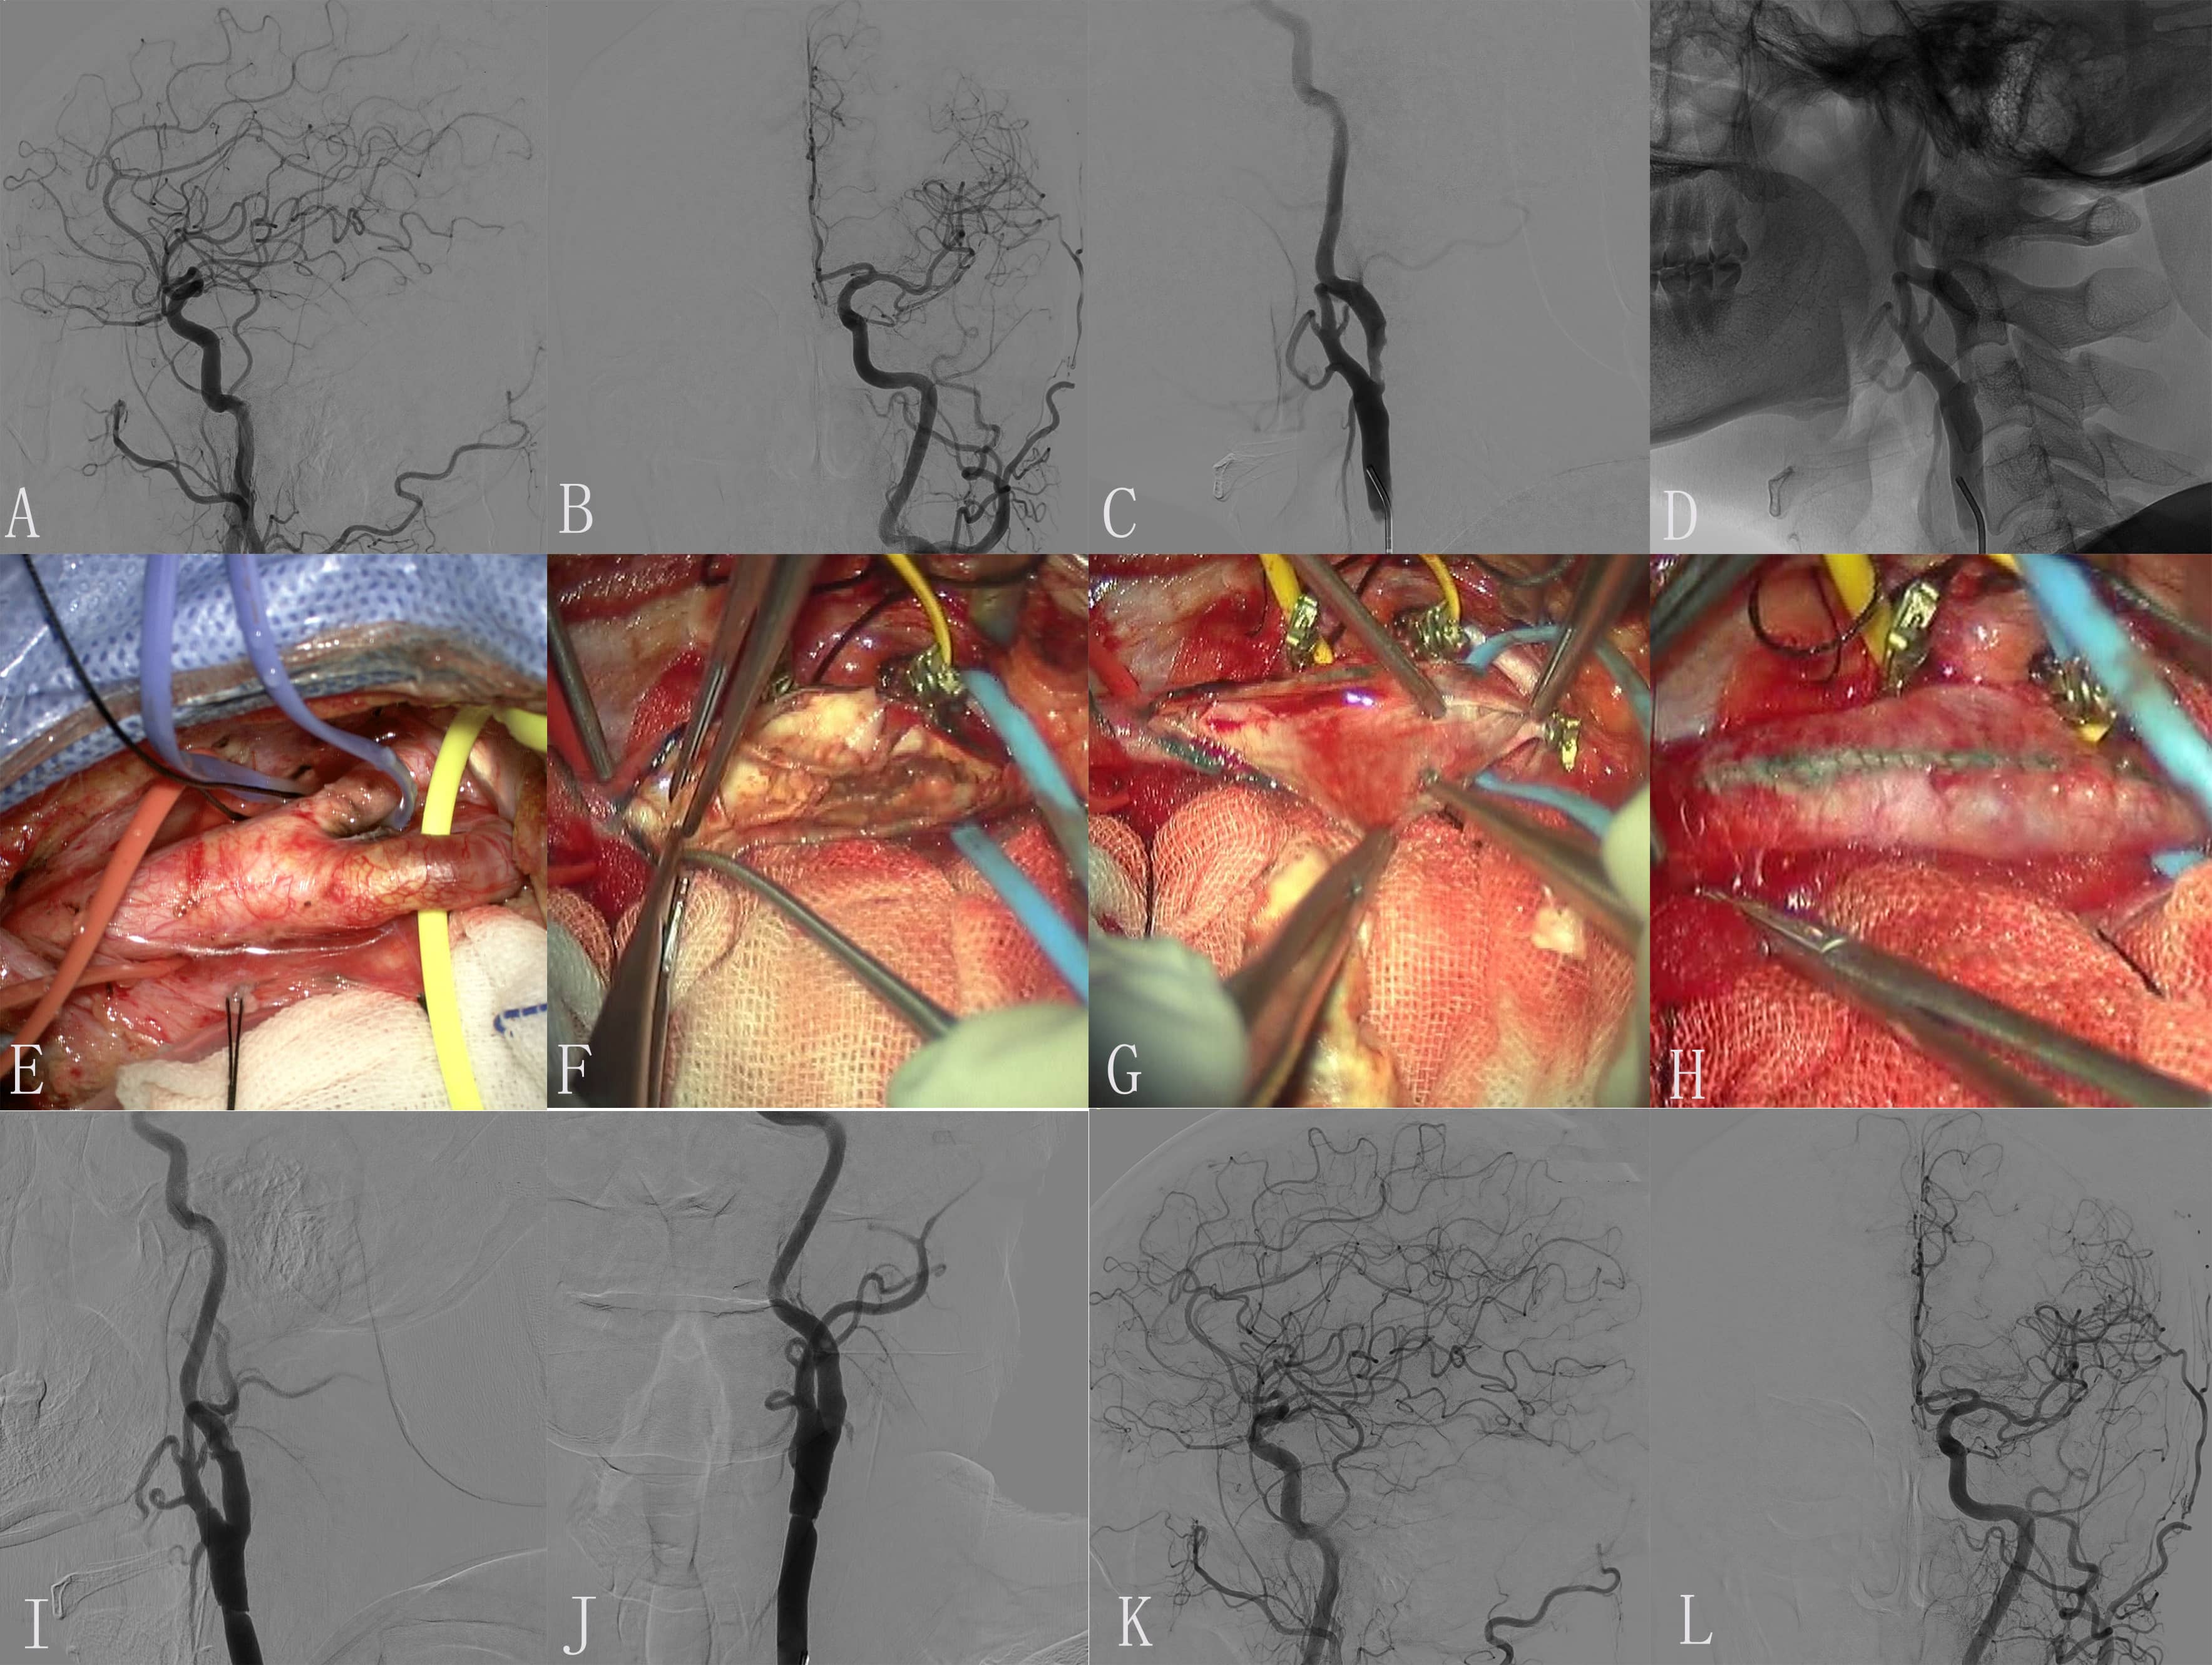

Fig. 3.Images of Case 3. Color Doppler ultrasonography of carotid artery on admission showed initial severe stenosis of the left internal carotid artery (ICA). The stenosis is greater than 90%. (A) Each branch was blocked by exposed responsibility carotid artery. (B) The endometrium of the common carotid artery (CCA) was dissected longitudinally and presented plaque. (C) Incision suture. (D) Intimal plaque. (E,F) Embolus was formed in a position with a large angle of carotid endarterectomy (CEA). (G,H) The imaging of ICA was significantly improved after 0.5 mg tirofiban was administered to the artery.